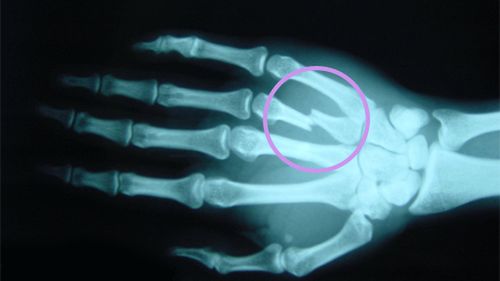

Najogólniej mówiąc, złamania dzielą się na zamknięte i otwarte, oraz z przemieszczeniem i bez przemieszczenia. Czym charakteryzują się poszczególne rodzaje?

• złamanie zamknięte - kość ulega złamaniu, jednak nie przebija skóry;

• złamanie otwarte - złamana kość przebija skórę i widoczne są jej odłamki w ranie;

• złamanie bez przemieszczenia - kość pęka, ale jej części pozostają na swoich miejscach;

• złamanie z przemieszczeniem - elementy złamanej kości przesuwają się względem siebie.

Przemieszczenia prawdopodobnie nie będziemy w stanie stwierdzić sami, dlatego powinniśmy zawsze postępować ostrożnie, tak, jakby faktycznie miało miejsce. W przypadku złamań zamkniętych i otwartych, raczej nie będziemy mieć wątpliwości i rozpoznamy je na pierwszy rzut oka.